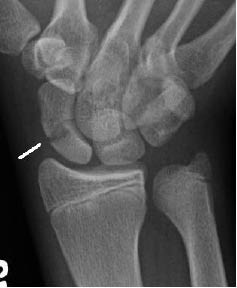

Figure 3: Scaphoid Fracture

Individuals who present with suspected scaphoid fractures with negative plain radiographs should be placed in a thumb spica splint and referred to an appropriate specialist for follow-up and possible repeat radiographic imaging. While this approach is acceptable, a large portion of these patients do not have scaphoid fractures and are placed in thumb immobilization unnecessarily.2,5 Unnecessary immobilization can lead to absenteeism at work and lost wages.